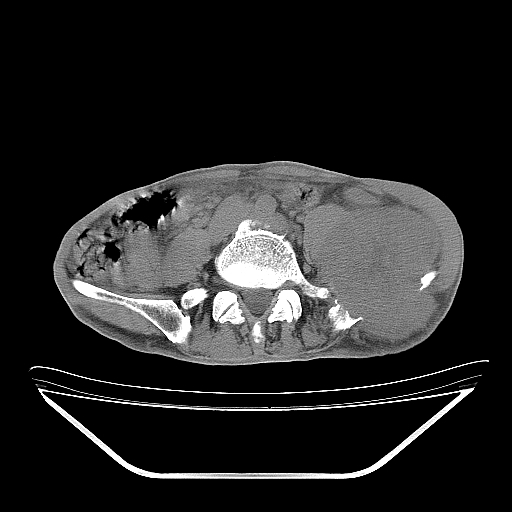

以下是引用天南地北在2007-10-4 18:01:00的发言:[br][br]考虑左髂部恶性肿瘤(溶骨性骨质破坏+软组织肿块影+残留骨质);以滑膜肉瘤可能性大。[br]建议穿刺活检

以下是引用liuyue在2007-10-4 23:38:00的发言:[br]左髂部恶性肿瘤,建议穿刺活检,或先做肺部检查,除外肺癌转移之可能。